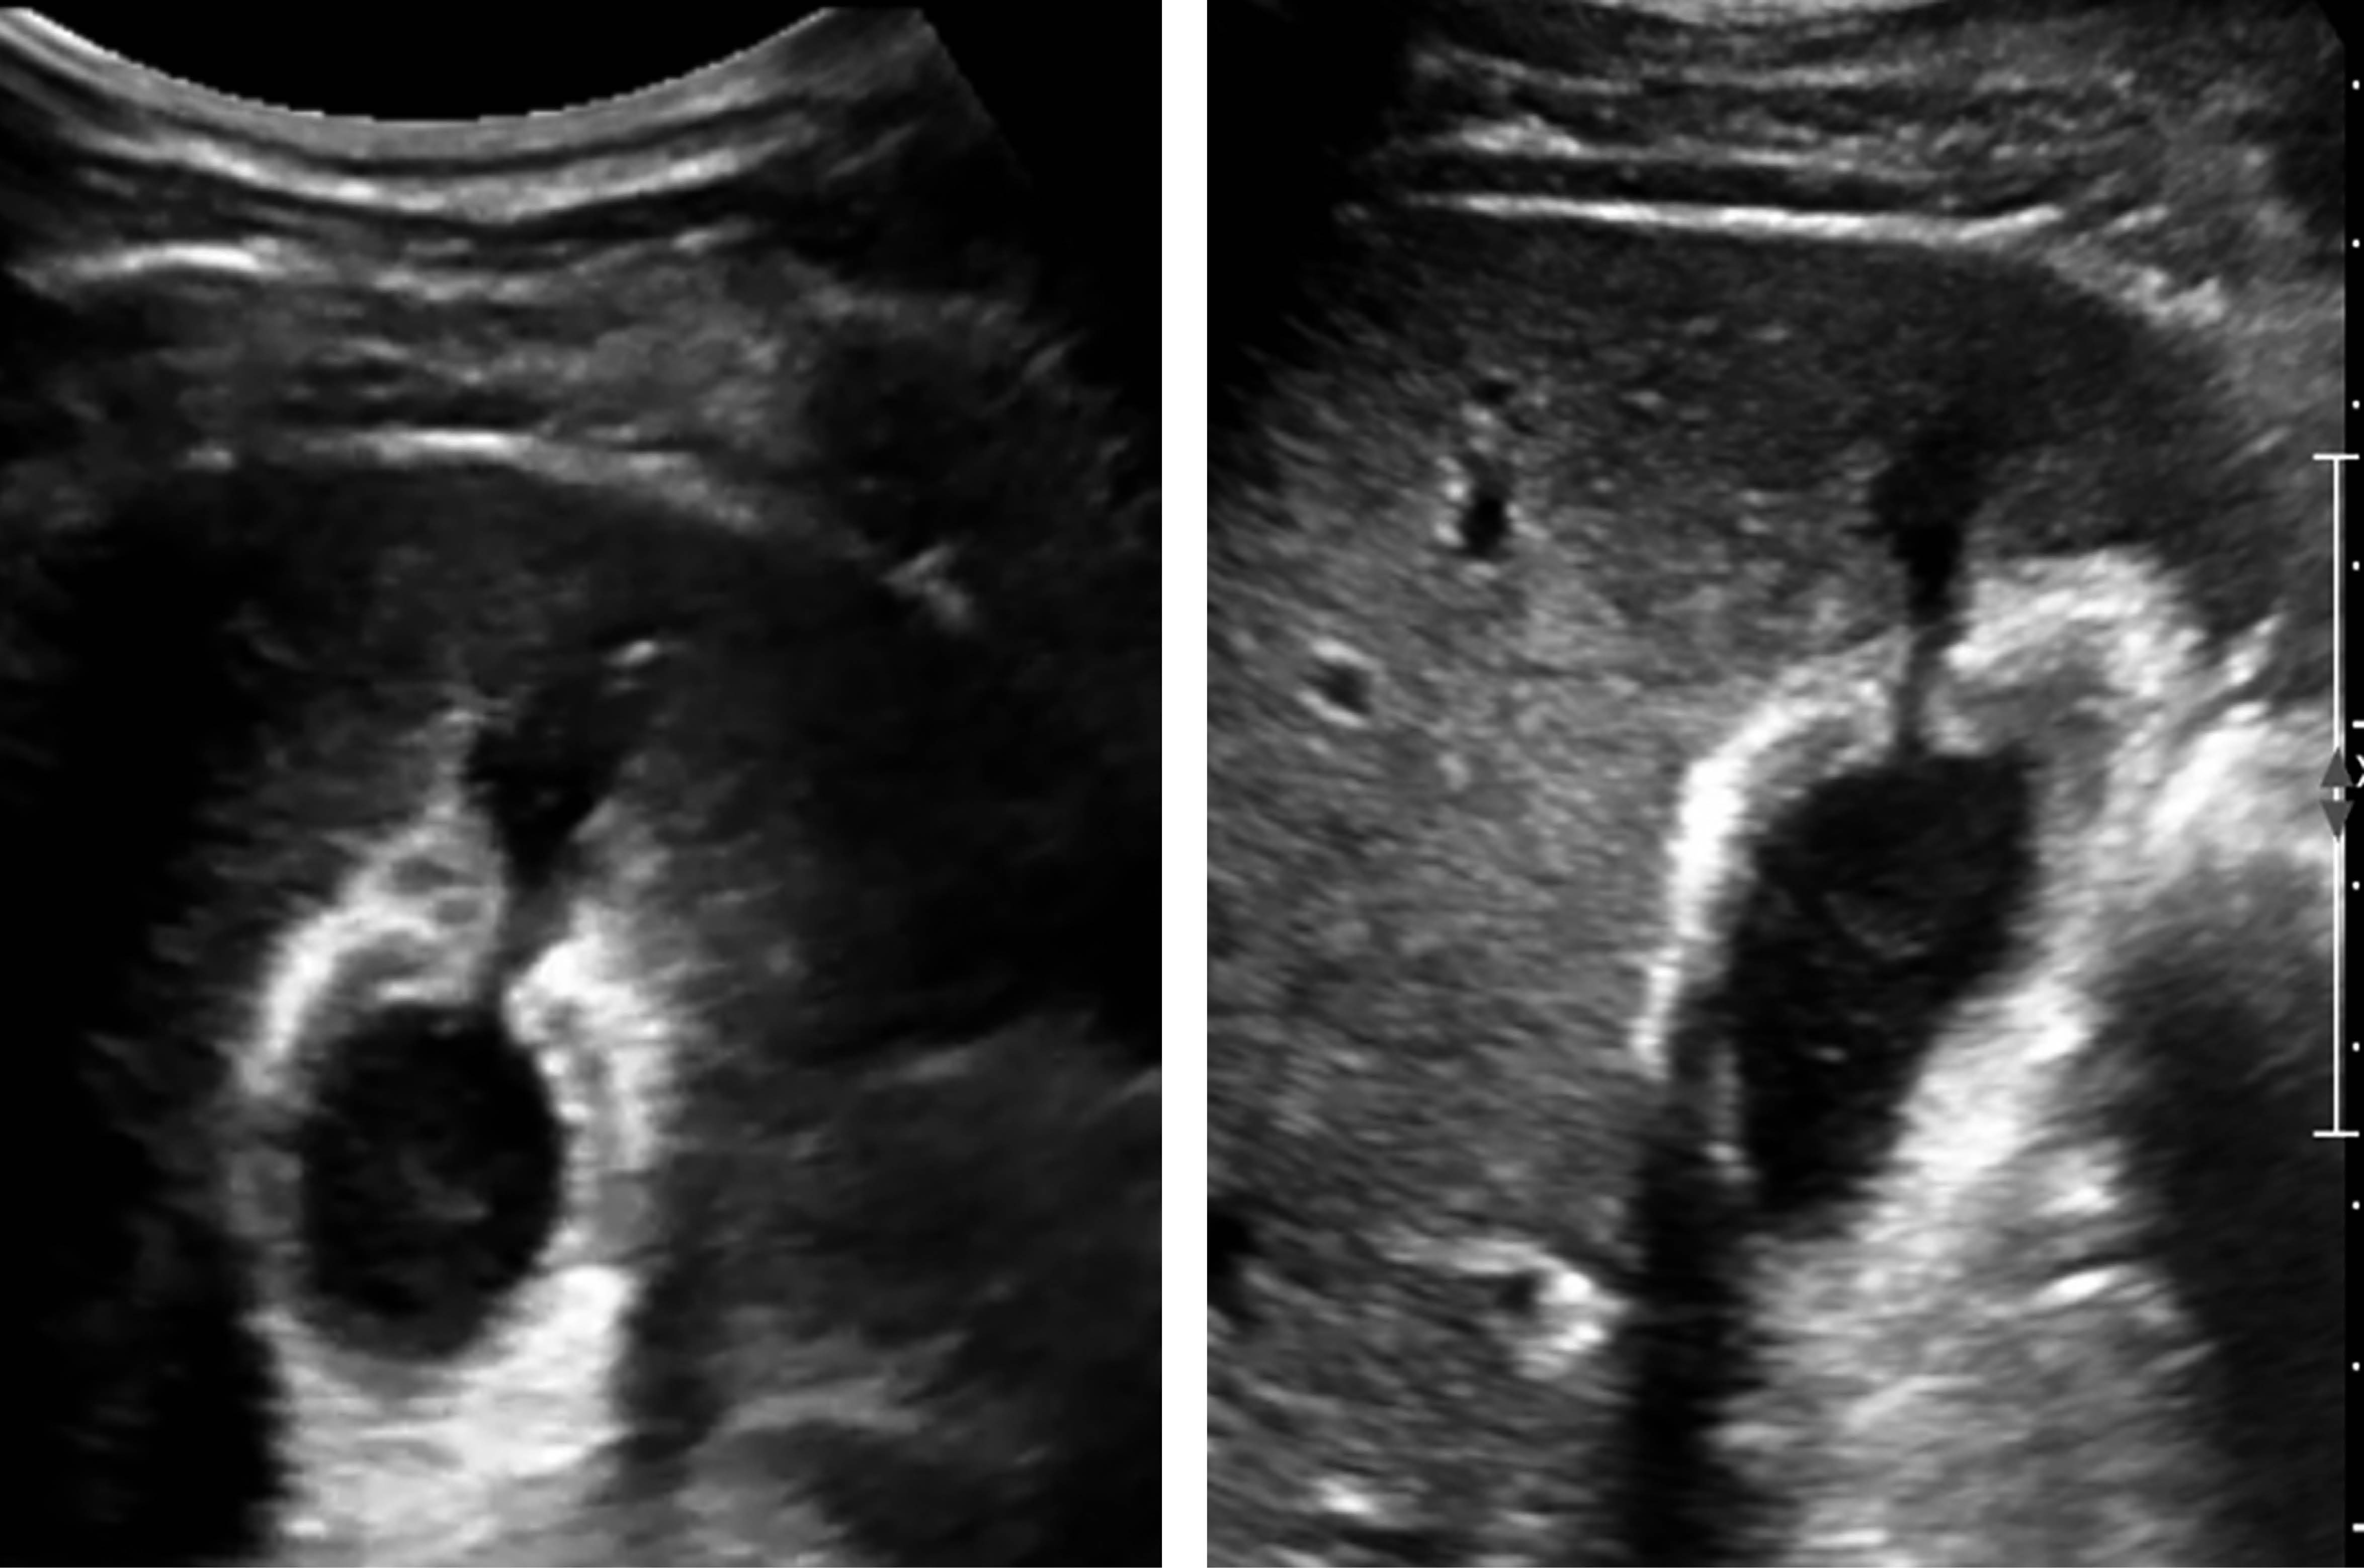

A control USG scan was performed, which reported the gallbladder with thickened walls up to 8 mm, peri vesicular edema, and loss of continuity at the level of the fundus where liquid of hypoechoic appearance like vesicular content of 3.2 cm3 (hemobilia), without evidence of free liquid in the abdominopelvic cavity were seen (Figure 5).

One month after his hospital discharge, he was seen as an outpatient without abdominal pain or changes that affected his quality of life, carrying out his daily activities. He was seen again seven months after his discharge with a new liver and biliary tract USG scan as control. No data of an acute inflammatory process in the gallbladder was observed (Figure 6). Also, clinically, he was asymptomatic, and it was decided to discharge him from the service.